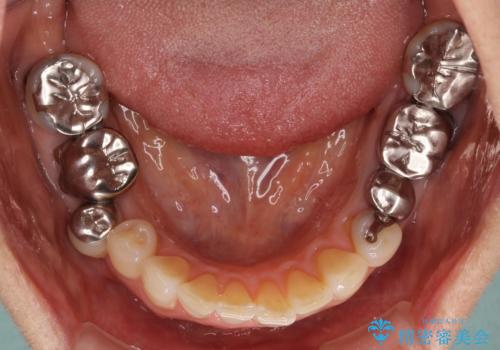

金属を全てセラミックに メタルフリー治療

- 口腔内にある銀歯を全て外したいとのことで来院された患者様です。

土台に含まれている金属も含め、口腔内の金属は全て除去し、抜歯しなければならない歯は抜歯し、オールセラミッククラウンやセラミックインレーにて治療することとしました。

上下奥歯の抜歯を同時期に行わず、下顎の治療を終えてから上顎を抜歯して治療を進めたため、1年ほどの期間を要しました。